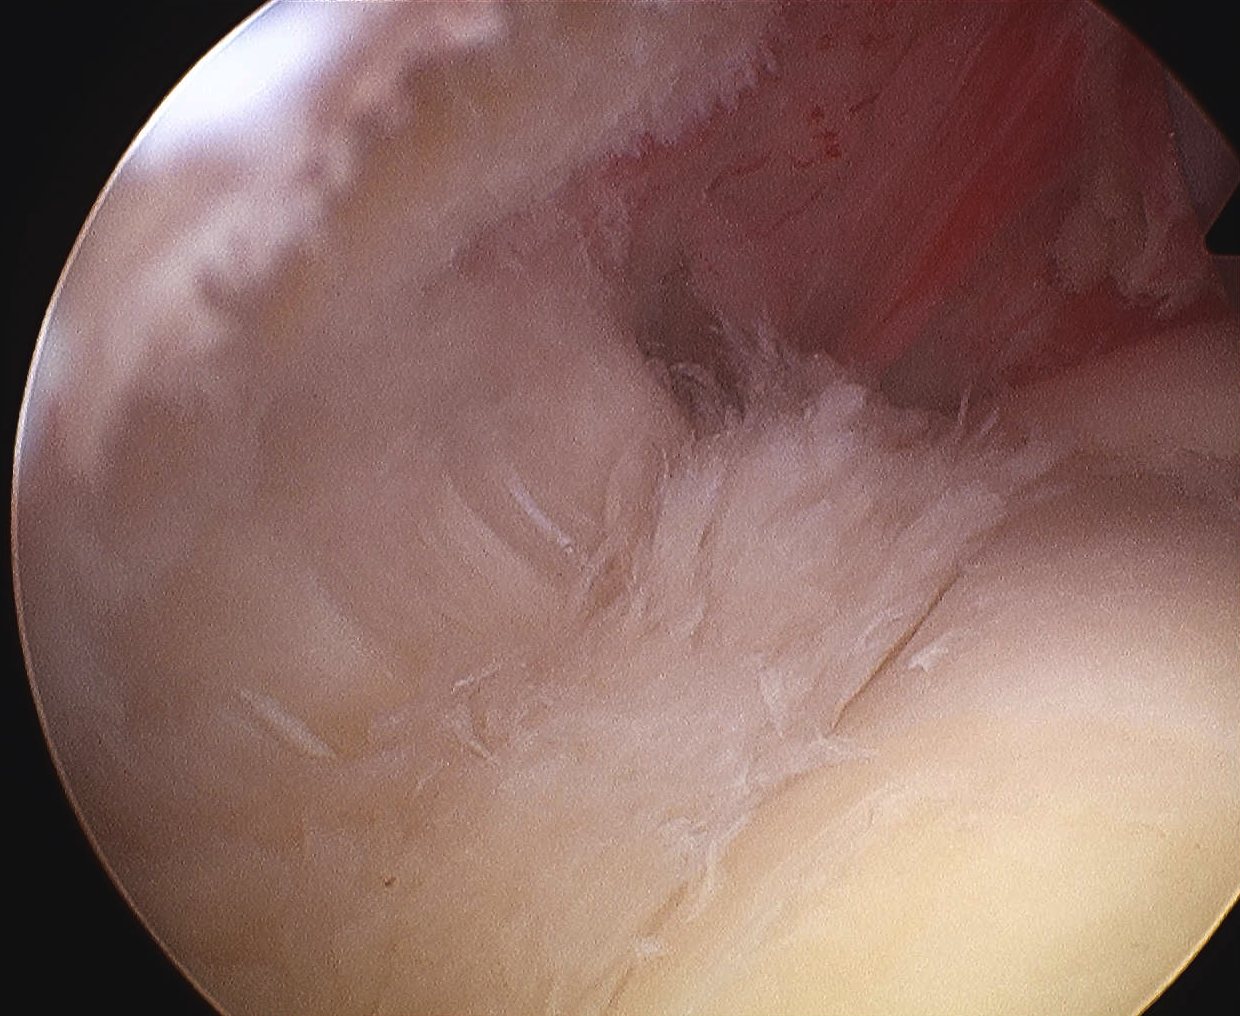

> 50% uncovering of footprint in glenohumeral joint